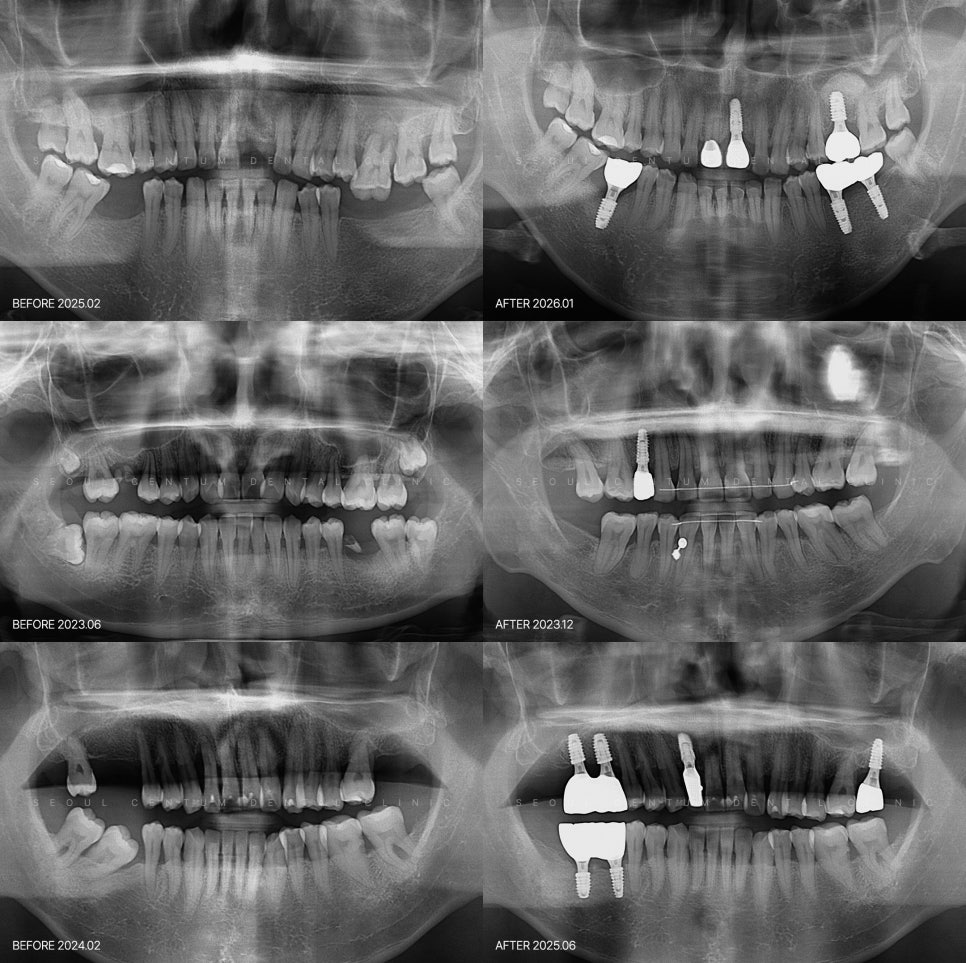

전신질환이 있을 때 임플란트를 고민한다면 당뇨임플란트 가능할까요? 당뇨 진단 이후 치과 치료를 앞두고 있다면 여러 가지 고민이 교차하기 마련일 거라 봅니다. 특히 임플란트는 혈당 상태나 회복 과정에 대한 우려로 인해 쉽게 결정을 내리기 어려운 경우도 많죠. 최근에는 전신 상태를 충분히 반영한 진단 시스템이 구축되어...